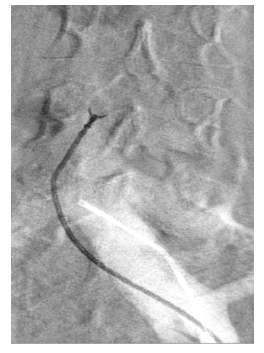

Consequently, a phlebography, a magnetic resonance, and a positron emission tomography (PET) scan were performed to clarify the etiology, which raised the suspicion of a leiomyoma of the IVC. The PET scan was conducted to determine whether the lesion exhibited high proliferation, which could indicate a malignant neoplasm. Nevertheless, the mass was identified as a low-proliferation lesion. The phlebography confirmed an occlusion of the inferior vena cava with repermeabilization above the known lesion, with slow progression of contrast. Subsequently, an endovascular biopsy, performed with a Cordis® biopsy catheter, confirmed the suspicion of a IVC leiomyoma. A left femoral access was obtained with a 9Fr introducer, the biopsy catheter was then advanced to the IVC wall, and a mass sample was collected, Figure 2 and 3. The biopsy was successful, with the histopathological examination reporting a myxoid leiomyoma.

Figure 3 Intra-procedural fluoroscopy image. The endovascular biopsy catheter is shown collecting IVC samples.